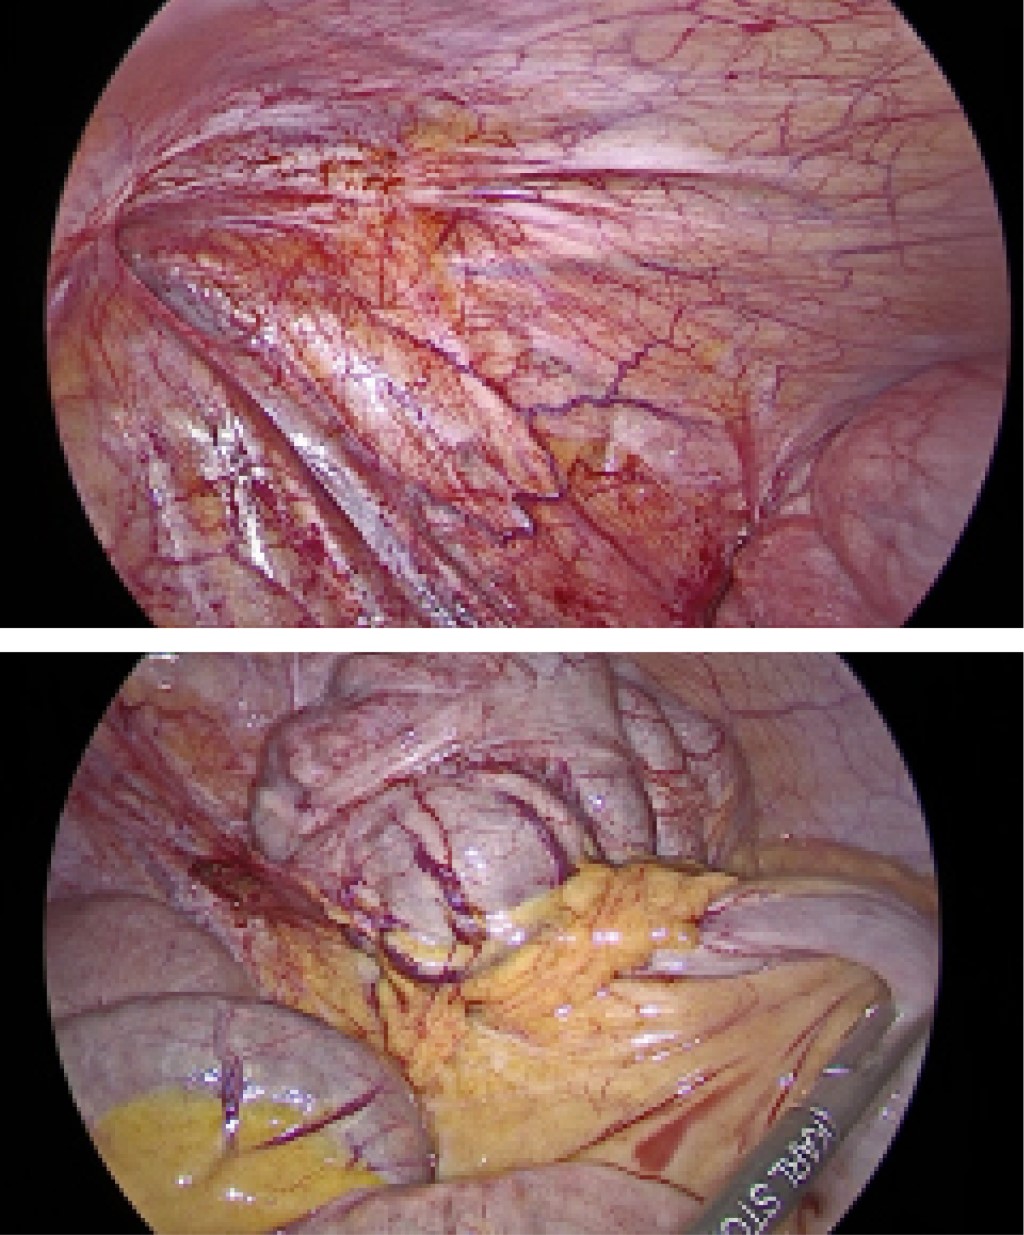

Introduction: appendicular neoplasms represent 1% of all colorectal cancers, one of the histological variants is appendiceal mucinous neoplasm, formerly known as mucocele. The clinical presentation is largely similar to that of acute appendicitis, so its preoperative diagnosis is rare. Clinically, patients present different symptomatology depending on the stage they are in, the most common manifestations are pain in the right iliac fossa, fever, palpable mass, abdominal distension, weight loss, anemia, chronic abdominal pain, infertility, among others. The defining pathologic characteristic of evidence of low-grade appendiceal mucinous neoplasm (LAMN) is invasion of the appendiceal wall, the presence of irregularity in the wall of the observed and the increase in thickness of the soft tissues can predict the malignancy of the tumor. Peritoneal involvement at the time of diagnosis can be up to 53%. The possibility of disease progression to pseudomyxoma peritoneal exists if dissemination occurs by rupture of the lesion and release of mucin into the peritoneal cavity. The treatment of LAMN always requires surgical management and the use of hyperthermic intraoperative chemotherapy in case of peritoneal involvement is still under debate. Case presentation: this case deals with a patient, 41 years old, who after three months with abdominal pain in the right iliac fossa, is taken to the operating room for a diagnostic laparoscopy due to the suspicion of a mucinous neoplasm, no mucinous lesions were found, an appendectomy plus cecectomy was performed. With stapler, pathology reported LAMN with serial involvement (pT4) and at six months a control laparoscopy with no evidence of mucinous lesions. The involvement of the serosa opened the discussion on whether hyperthermic intraperitoneal chemotherapy is necessary when there are no visible mucinous lesions and there was no mucin contamination. Conclusions: the literature to date has no clear evidence on the prognosis of this type of injury and whether it is useful or not. The challenge of this diagnosis will be to have a multicenter prospective study that allows the development of care protocols with strategic treatments.

Figure 4